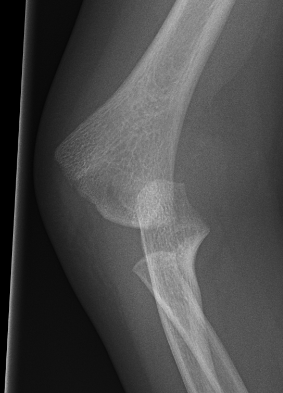

Xray

Distal physis not ossified < 1 year

- radius and ulna lose normal association with distal humerus

- posteromedial displacement of the ulnohumeral joint

- appears like an elbow dislocation

- disruption of radio-capitellar line